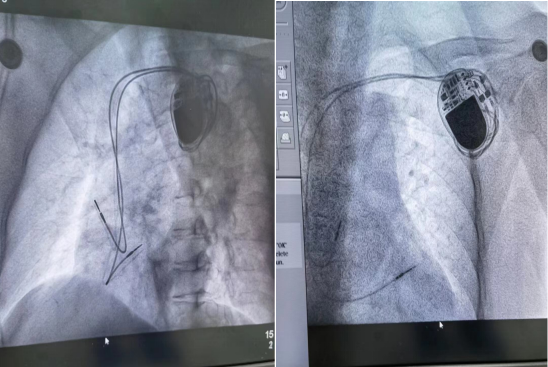

本次手术由李勇主任主刀,主治医师黄生华协助,以及医护团队默契配合、细致操作,郭阿姨成功接受了在DSA下实施双腔永久性起搏器植入术。此例手术为我县首例,手术过程顺利,用时1小时30分钟,术后,起搏器工作正常,郭阿姨安返病房。术后第一天,心电监护提示窦性心律与起搏心律交替,郭阿姨感觉良好,无明显不适症状。术后一周如期拆线,切口愈合良好。在医护人员详细告知起搏器术后各项注意事项后,郭阿姨正常出院。